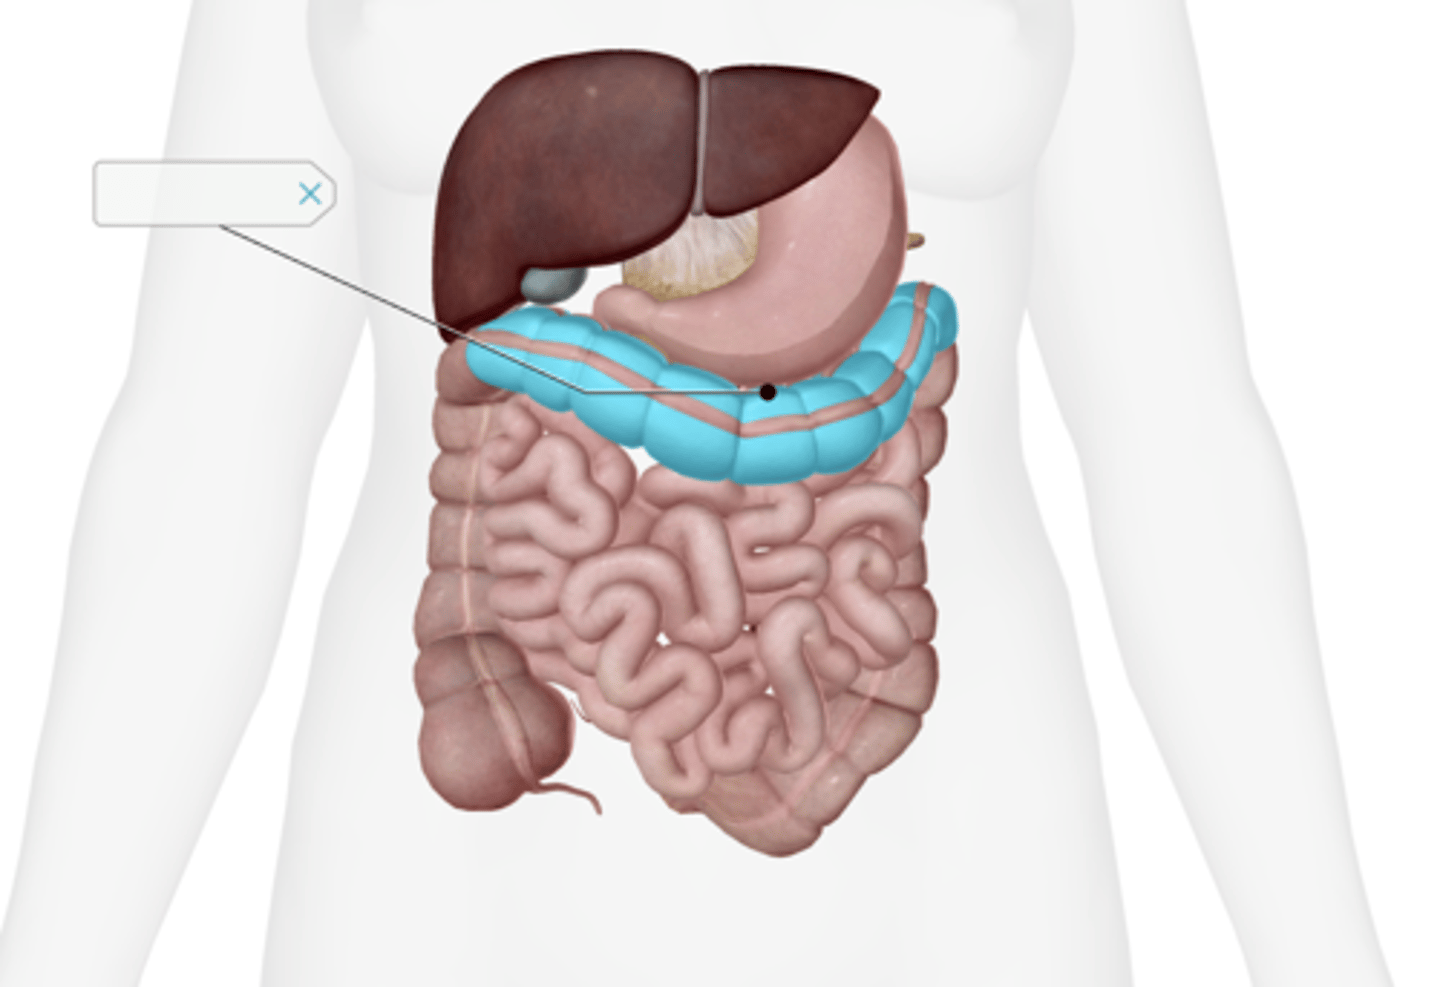

Transverse colon